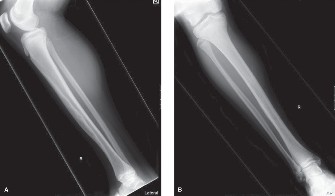

1. Plain Radiographs (AP/Lateral): Initial assessment of the lesion, cortical integrity, and overall bone architecture. Used for Mirel score size and character assessment.

2. Computed Tomography (CT) Scan: Provides detailed information on cortical destruction, medullary canal involvement, soft tissue extension, and precise lesion dimensions. Crucial for planning implant length and diameter, and for assessing the extent of lytic defects requiring augmentation.